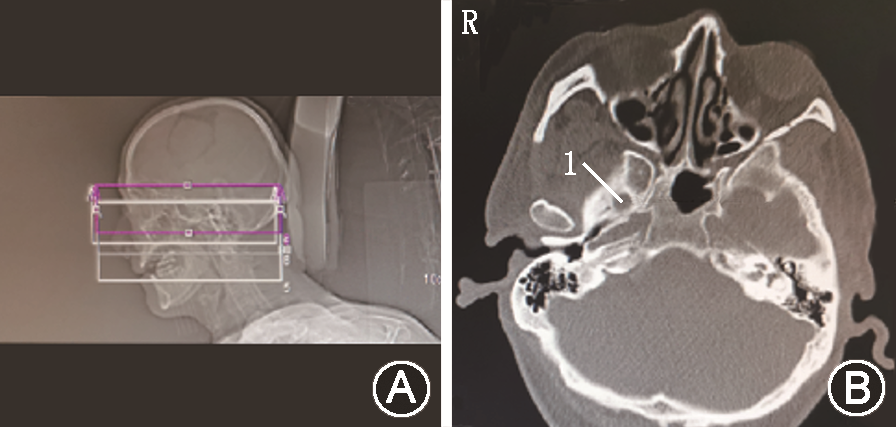

予以原方案继续口服镇痛药物,同时行眶上神经阻滞,利多卡因凝胶贴膏(北京泰德制药股份有限公司,国药准字H20180007,规格:700 mg)外贴,1贴/d,静脉抗生素抗感染、内分泌科会诊稳定血糖。入院调整3 d后,行局部麻醉下CT引导经皮穿刺半月神经节球囊压迫治疗(percutaneous microballoon compression,PMC)[3],因患者有强直性脊柱炎病史,不能平卧,予以多个体位垫辅助固定(图1),术前规划穿刺路径困难(图2)。按经典Hartel入路穿刺进入卵圆孔内口(图3A)[4],退出针芯,置入球囊导管,使远端Mark点与岩锥顶端平齐(图3B),注入30%碘海醇造影剂0.6 ml充盈球囊(图3C),球囊CT三维影像成“梨”形(图4),压迫半月节200 s,询问患者自诉右面部皮肤感觉轻度麻木,原疼痛基本消失,NRS评分2分,遂释放球囊内造影剂,拔出于球囊导管和穿刺针,结束手术。